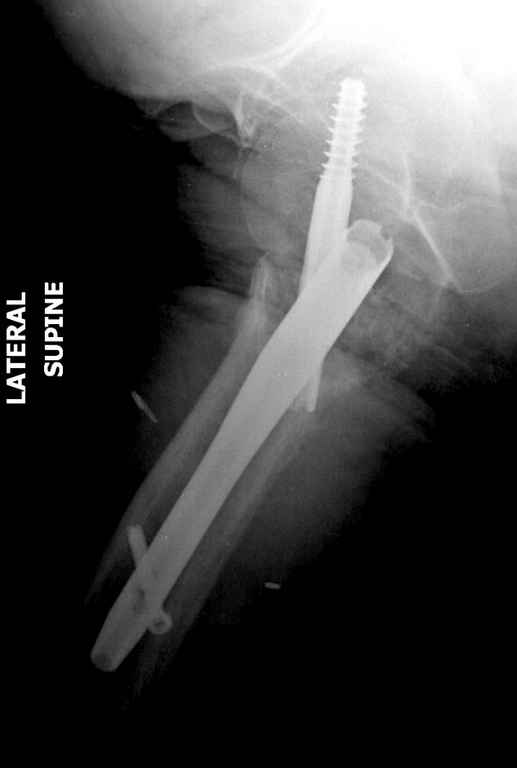

Перелом тут больше подвертельный. Нагрузка без торцевого упора на уровне перелома привела к телескопированию отломков на стержне. Ну и варус небольшой тоже свою лепту внес - если бы его не было, контактирующие латеральные стенки обоих отломков предотвратили бы укорочение, да и срослось бы за пару месяцев. А раз не срослось, упора отломков нет, более слабым местом оказались не нижние винты, а кость в головке и шейке. Так что надо было хотя бы удалить нижние винты до начала полной нагрузки.

На мой взгляд, причиной телескопирования явилось несоответствие диаметра гамма нэйл с диаметром канала подвертельного отдела бедра: обратите внимание на величину протрузии шеечного винта и величину медиализации дистального фрагмента - они одинаковы, смещение или телескопирование фрагментов происходило до того момента, пока гамма нэйл не упёрся в медиальный кортекс и образовалось пространство между латеральным

кортексом и латеральной поверхностью гвоздя.

Диаметр гаммы в диафизарной части ~11 мм. А диаметр канала, тем более у пожилых с остеопорозом, может быть мм 15. Даже рассверливать обычно не приходится, после формирования широкого канала в вертельной области можно сразу толкать гвоздь, он влетает, как карандаш в стакан. Так что соответствия диаметров не бывает никогда. Однако представленная ситуация случается далеко не каждый раз. Если гвоздь в центральном отломке входит чуть медиальнее верхушки вертела, и идет вдоль передне-латеральной стенки центрального отломка, то все будет хорошо.

В приложении похожий пример, к счастью, пациентка появилась не после, а "за полчаса" до протрузии. Пересинтезировали с исправлением ошибок.